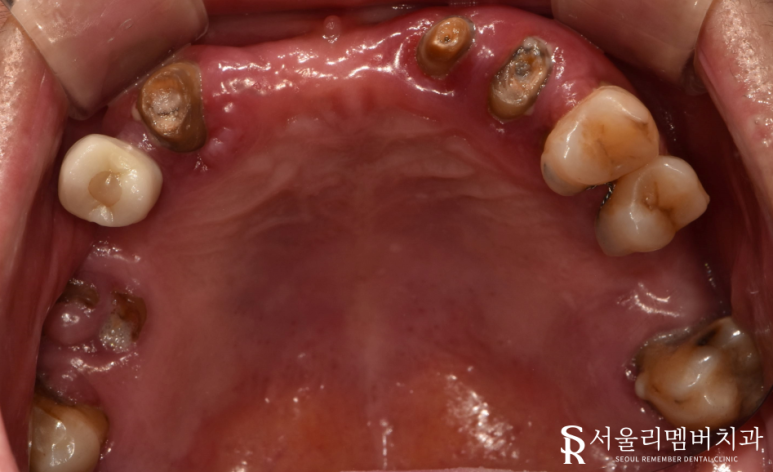

앞니 상실 및 잔존 치근

구강위생 불량 (다수의 치석, 충치, 잇몸 염증)

정출

치경부 드러남

크게 4가지를 꼽을 수 있겠군요.

엑스레이를 보면 남아있던 치아 대부분에서 치근단 염증(뿌리)이 진행되고 있었는데요.

조금만 내버려 둬도 곧 자연 발치가 될 것으로 예상되었습니다.

자연치를 살릴 수 있다면 살리는 것이 좋겠으나

안타깝게도 살릴 수 있는 것은 존재하지 않았습니다.